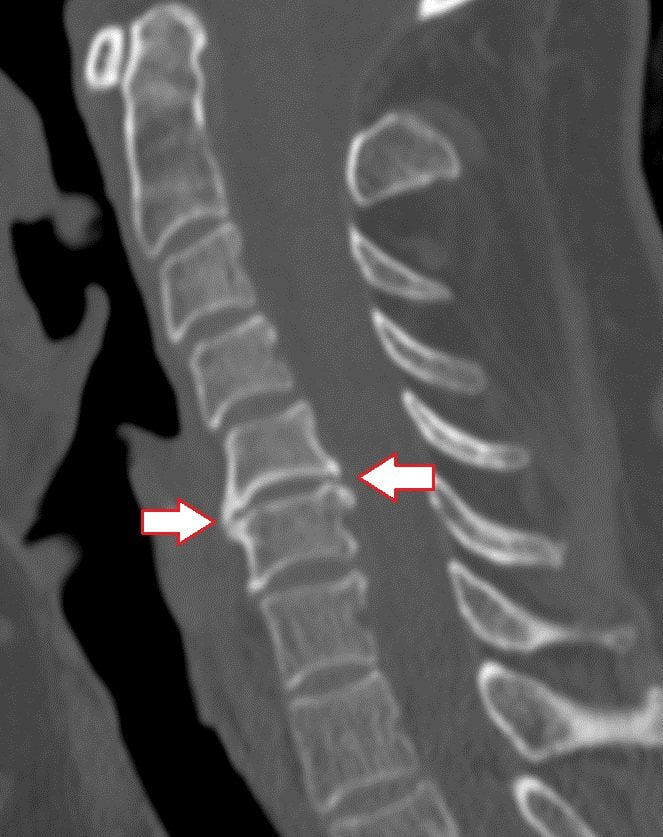

Постоянная травматизация связок, суставов, позвонков в итоге вызывает нарушение их нормального строения. В дальнейшем в их тканях откладываются соли кальция, что вызывает оссификацию структур позвоночника. На боковых и передних поверхностях позвонков образуются остеофиты – патологические костные наросты, которые на рентгенограммах имеют вид усиков, крючков или клювов.

Классификация спондилеза в зависимости от рентгенологических признаков:

- Новообразованные остеофиты имеют небольшой размер, не выходят за пределы тел позвонков. Спондилез 1 степени обычно протекает бессимптомно.

- Остеофиты разрастаются по направлению друг к другу, огибая межпозвоночный диск. В некоторых случаях костные наросты образуют неоартрозы.

- Сросшиеся остеофиты формируют костную скобу, которая плотно соединяет тела двух смежных позвонков. Это приводит к нарушению функционирования позвоночно-двигательного сегмента.

Для диагностики патологии используют рентгенографию и МРТ. Магнитно-резонансная томография является более информативной и позволяет выявить патологические изменения позвоночника на самых ранних стадиях.